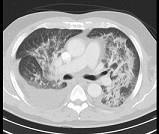

问题 男,51岁,呼吸困难,心悸,咳大量粉红色泡沫痰,结合CT,最可能的诊断是 ( )

选项 A.肺泡性肺水肿 B.间质性肺水肿 C.肺泡癌 D.肺泡蛋白沉积症 E.肺结核

答案 A